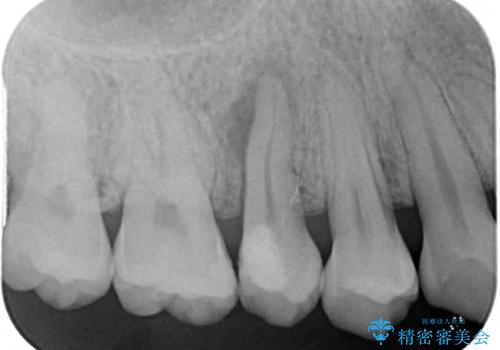

根管治療を行った奥歯は、再発防止や残された歯質を守るため、クラウンによる補綴治療が必要となります。

補綴後6ヶ月経過しレントゲンを撮影したところ、根尖周辺の病変が消失していることが確認できました。